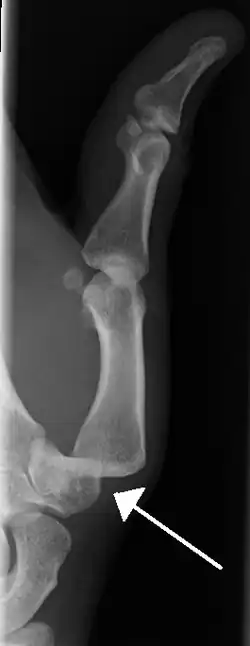

Radiograph of right fifth finger dislocation

• Interphalangeal (IP) or metacarpophalangeal (MCP) joint dislocations[41]

• In the United States, men are most likely to sustain a finger dislocation with an incidence rate of 17.8 per 100,000 person-years.[42] Women have an incidence rate of 4.65 per 100,000 person-years.[42] The average age group that sustain a finger dislocation are between 15 and 19 years old.[42]

• The most common dislocations are in the proximal interphalangeal (PIP) joints.[8]